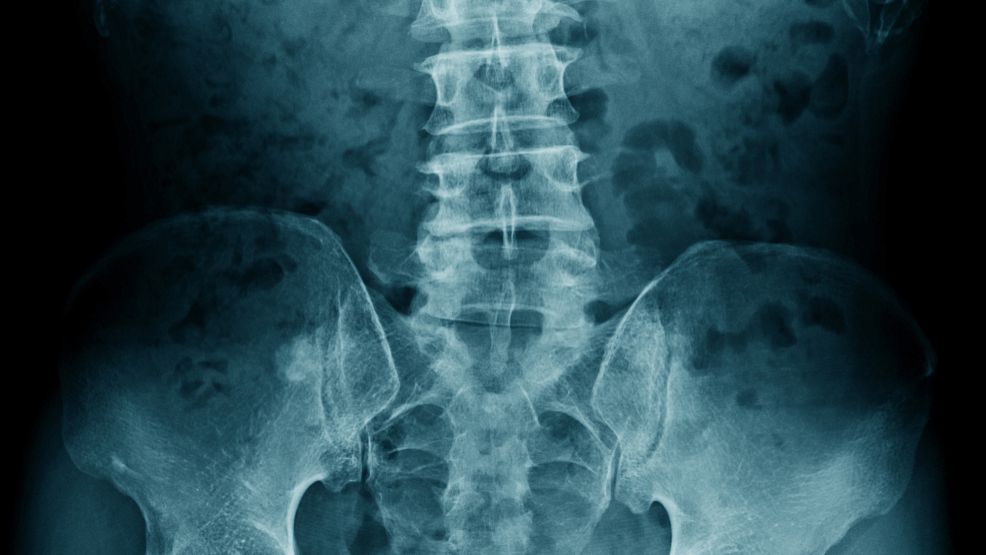

在选择医院时,除了看医生的专业水平,还要考虑医院的环境和设备。比如,一些医院配备了先进的内窥镜检查设备,可以更直观地观察肛门内部情况,帮助医生做出更准确的诊断。此外,医院的医疗团队也是关键,他们不仅要具备扎实的医学知识,还要有丰富的临床经验。